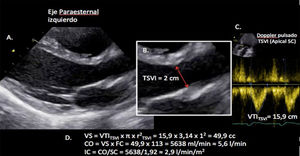

Valoración del volumen sistólico (fig. 2)Se puede realizar por medio de la integral velocidad-tiempo (IVT) y el diámetro del tracto de salida del ventrículo izquierdo (TSVI).

Estimación del volumen sistólico (VS) y del gasto cardiaco (CO) a través de la integral de velocidad (VTI) y radio (r) del tracto de salida del ventrículo izquierdo (TSVI). A) Paraesternal izquierdo ventrículo izquierdo en sístole. B) Zoom TSVI. C) Doppler pulsado TSVI 5C apical. D) Cálculos.

Un IVTTSVI<11cm se correlaciona con un índice cardiaco <2 l/min17,18.